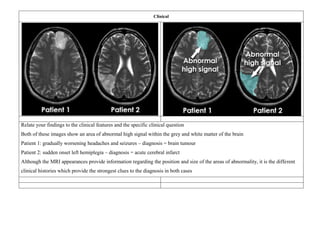

Clinical

Relate your findings to the clinical features and the specific clinical question

Both of these images show an area of abnormal high signal within the grey and white matter of the brain

Patient 1: gradually worsening headaches and seizures – diagnosis = brain tumour

Patient 2: sudden onset left hemiplegia – diagnosis = acute cerebral infarct

Although the MRI appearances provide information regarding the position and size of the areas of abnormality, it is the different

clinical histories which provide the strongest clues to the diagnosis in both cases